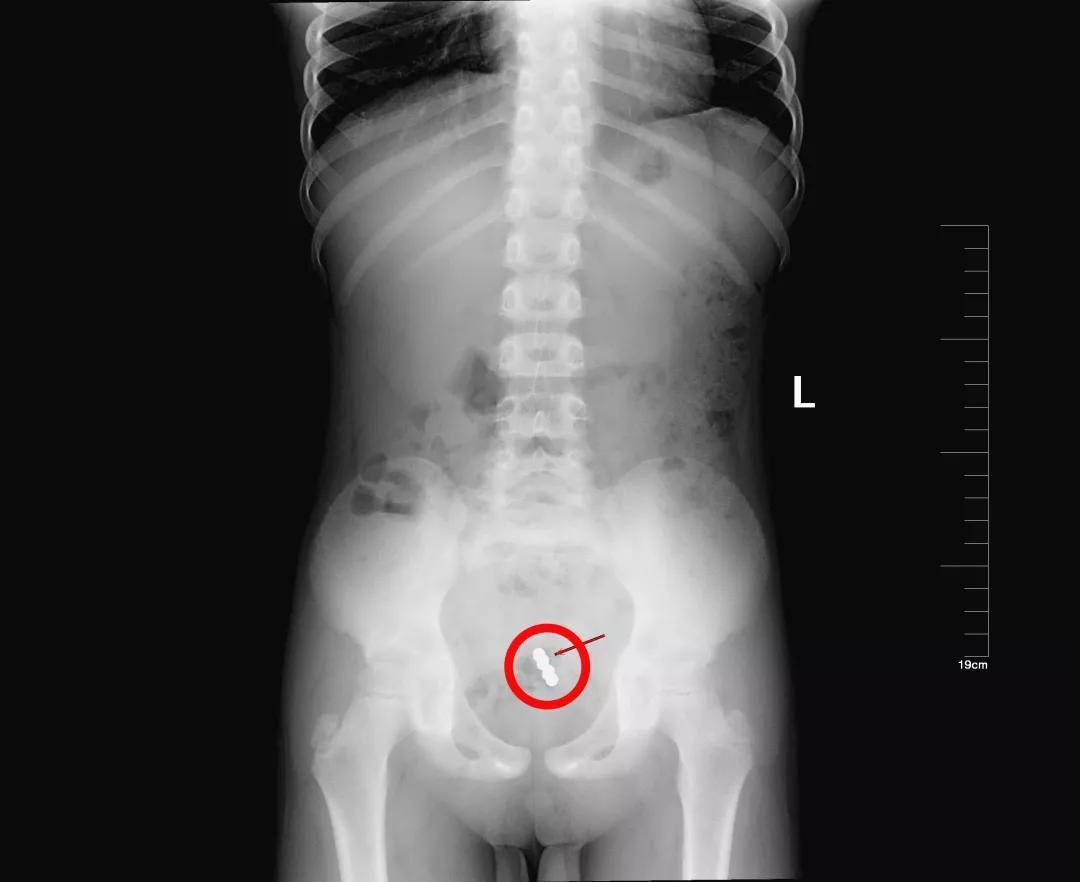

2岁·磁力珠

1天余前误吞磁力珠9颗,每颗直径2mm左右,误服时孩子主诉食管部位不适。

单个磁铁的危险性不大,但是多个磁铁进入体内后,在不同的消化道会紧紧地吸在一起,强烈的吸力会导致消化道穿孔。